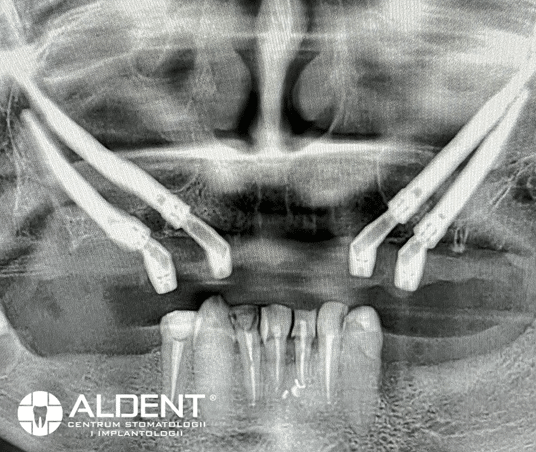

Implanty zygomatyczne są rewolucyjnym rozwiązaniem dla pacjentów z rozległymi zanikami kostnymi szczęki. Ten rodzaj implantów dedykowany jest bezzębnym pacjentom, u których jeszcze kilka lat temu było niemożliwe uzupełnienie braków zębowych tradycyjnymi implantami. Implanty zygomatyczne opracował szwedzki profesor Per-Ingvar Branemark. Ów twórca leczenia implantologicznego odkrył, że kość jarzmowa ma odpowiednią strukturę i objętość pozwalającą na osteointegrację implantów, dzięki temu dał szansę wielu pacjentom na komfortową odbudowę utraconych zębów. Implanty zygomatyczne wprowadzane są w odcinkach bocznych w okolicę kości jarzmowej, dlatego nazywane są też implantami jarzmowymi. Charakteryzują się tym, że są znacznie dłuższe od tradycyjnych implantów. Ich długość wynosi od 30 do ponad 50 mm. Wykonane są w całości z tytanu czyli materiału kompatybilnego i biozgodnego z organizmem człowieka.

Implanty zygomatyczne wprowadzane są pod kątem 45 stopni do kości jarzmowej. Dzięki wielopunktowemu zakotwiczeniu kortykalnemu oraz gwintowanej konstrukcji wierzchołka, zapewniają one odpowiednią stabilność uzupełnienia protetycznego. Wykonane z tytanu, są biokompatybilne i bezpieczne dla organizmu pacjenta.

Podczas pierwszej wizyty przeprowadzamy szczegółowy wywiad medyczny oraz badanie kliniczne jamy ustnej. Niezbędnym elementem diagnostyki jest wykonanie tomografii komputerowej 3D (CBCT), która pozwala na precyzyjne ocenienie warunków kostnych pacjenta i szczegółowe zaplanowanie zabiegu. Po kwalifikacji pacjenta do zabiegu, ustalamy termin zabiegu i przekazujemy zalecenia przedzabiegowe.

Przed zakwalifikowaniem pacjenta do zabiegu implantologicznego, w klinice CSK Aldent przeprowadzamy szczegółowy wywiad medyczny oraz dokładne badanie kliniczne jamy ustnej. Naszym priorytetem jest bezpieczeństwo i komfort pacjenta, dlatego każda konsultacja rozpoczyna się od precyzyjnej diagnostyki z wykorzystaniem stożkowej tomografii komputerowej (CBCT). Ta zaawansowana metoda obrazowania pozwala naszym implantologom na maksymalne wykorzystanie podłoża kostnego pacjenta oraz na precyzyjne zaplanowanie każdego zabiegu.